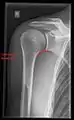

Projectional radiography views of the shoulder include:

- Transaxillary projection

The arm should be abducted 80 to 100 degrees. This method reveals:[24]

- The horizontal alignment of the humerus head in respect to the socket and the lateral clavicle in respect to the acromion

- Lesions of the anterior and posterior socket border, or of the tuberculum minus

- The eventual non-closure of the acromial apophysis

- The coraco-humeral interval

CR. shoulay film.

Transaxillary conventional radiography

Y-projection conventional radiography